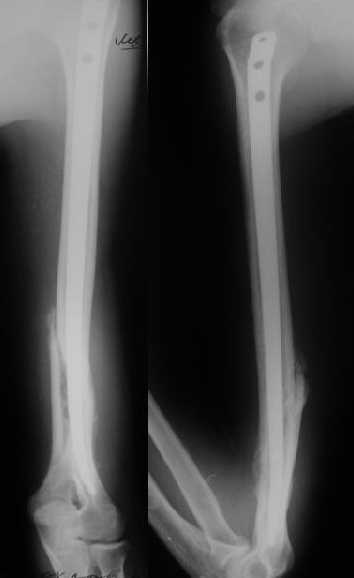

Огромное спасибо всем принимающим участие в дискуссии. Вначале отвечу на поступавшие персональные вопросы: 1. обстоятельства травмы - соревнования по армрестлингу (от себя замечу, что у военных нередкая травма в последнее время! На мой взгляд это связано с вовлечением в это дело неподготовленных людей - командирам нравится, т.к. в плане реквизита намного легче организовать чем традиционное перетягивание каната...). 2. в отношении провокационной составляющей - она присутствует, но лишь в той степени в какой любое инициирование дискуссии несет в себе элемент провокации... 3. про актуальность консервативного лечения - мне кажется это актуально всегда и при любой локализации если врач владеет методом, например, часто наблюдал великолепные функциональные результаты консервативного лечения переломо-вывихов голеностопных суставов... Тут только надо помнить, что "консервативное" это тоже лечение (контроль, тяги, перекладывание повязок), а не просто накладываем гипс и через энное время говорим, что не получилось и берем на операцию.

Теперь непосредственно по больному. Лечим функциональной повязкой, добились вот чего (приложение). Будем признательны за дальнейший комментарий - мое мнение, что можно продолжить без операции.

Юрий Алексеевич Булахтин